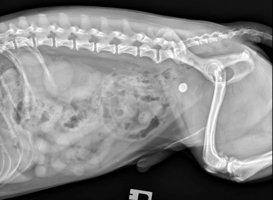

feature-img